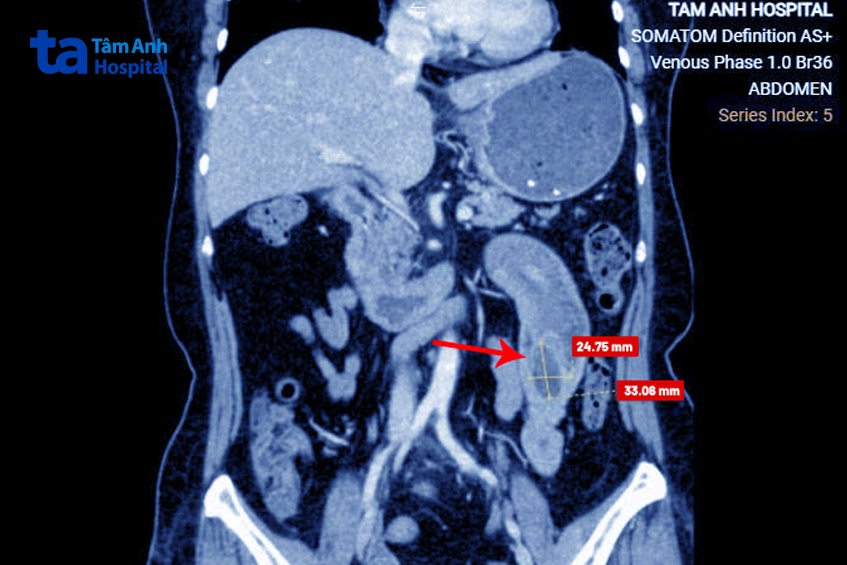

Kết quả chụp CT đa lát cắt phát hiện cuối đoạn ruột lồng của bà Thủy có khối u 2,5×3 cm. Vách u không ngấm thuốc, bờ đều, không thấy hạch hay các vi khối ngấm thuốc xung quanh.